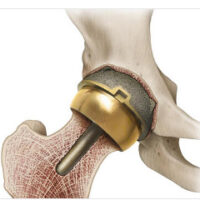

BHR illustration in bone

Everything changed in the 1990s.

British surgeon Derek McMinn—along with colleagues like Ronan Treacy—rethought the entire concept.

Key improvements:

• Modern metal-on-metal bearings

• Better implant design

• Improved surgical technique

👉 The breakthrough moment:

• July 30, 1997 – the first modern

Birmingham Hip Resurfacing was implanted